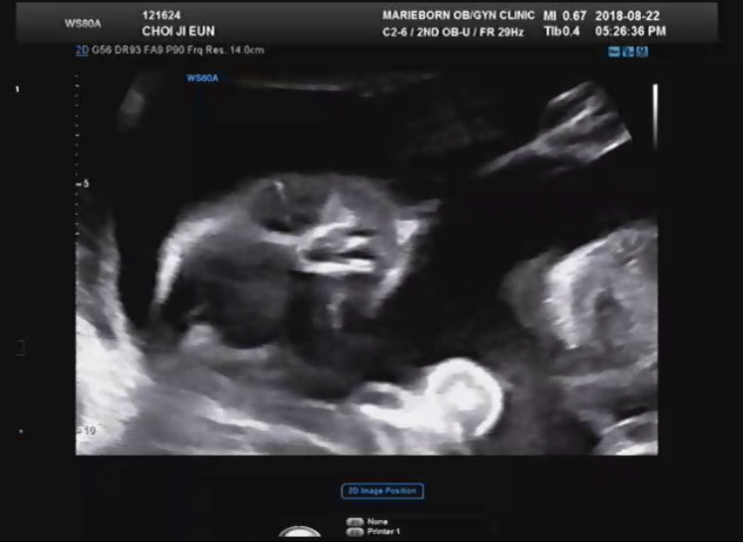

[⚝별하이야기/임신9주-임신14주]너만 건강하면..

아침부터 엄청엄청 찌는 날씨에요. 밖에 열일하시는 우리집 바깥양반..신랑은 엄청 더울텐데,, 저녁엔 맛있...